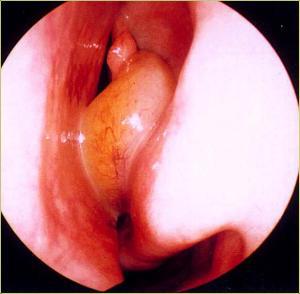

在鼻内镜的直视下手术,保留鼻腔鼻窦的生理功能,扫净病灶,改善和重建鼻及鼻窦的通气引流,恢复粘膜(纤毛及腺体)的形态和生理功能,达到治愈 目的。手术时,先以CT片和鼻内窥镜进行精确定位左右4对:称额窦、上颌窦、筛窦和蝶窦炎症组织和窦口位置,在麻醉的帮助下,借助美国美敦力鼻窦电动刀及美国杰西低温等离子消融系统下进行精确的开口引流、清除周围4对窦腔炎症,快速治疗鼻窦炎。![]()

鼻窦炎治疗手术中

“多窦一清”技术能一次性精确“扫净”四对鼻窦炎症,避免“漏诊盲区”、迁延其它鼻窦复发;同时结合功能性鼻腔术后修复和绿色康复技术,轻松清除额窦、上颌窦、筛窦和蝶窦等合并症,迅速恢复鼻部功能,终止疾病危害,治疗恢复期比同等手术缩短,被称为“多窦一清”高端技术。患者手术 后普遍反映,“扫净”疗效理想,好的快,多窦一清鼻窦手术“多窦一清”技术常用于额窦、上颌窦、筛窦和蝶窦炎症同时进行清除。它为鼻窦开 “窗”术引流做到不漏诊,出血很少、痛苦很轻、恢复快,患者认可度较高。